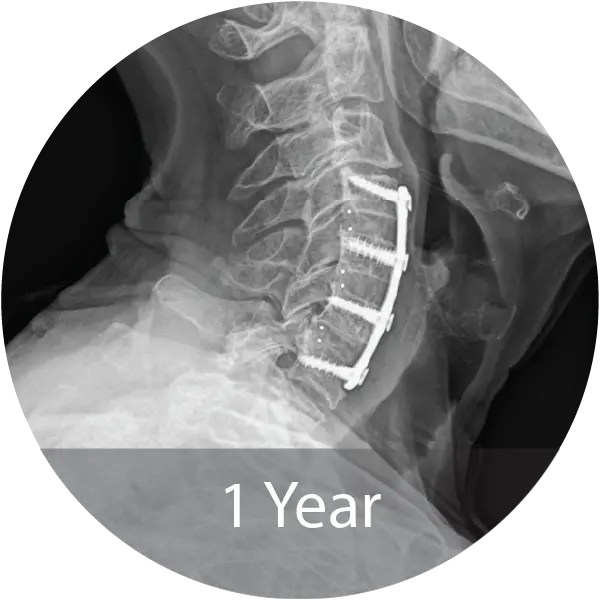

Case of an 80-year-old female with cervical degenerative disc disease and stenosis treated with a 3-level ACDF using NMP® Fibers. Reported 12-month fusion, no adverse events, complete pain resolution, and excellent handling characteristics.

Two case series including a lumbar case (59-year-old female, 1 pack/day smoker) treated with L4–S1 ALIF with posterior fixation and a cervical case (60-year-old female, 1.5 pack/day smoker) treated with 3-level ACDF demonstrated solid arthrodesis by 9 months, significant improvements in pain and disability scores, no complications, and return to work. A cost analysis showed a 26–29% reduction in biologic cost per case when transitioning from INFUSE® and i-FACTOR® to NMP® Bioimplant, translating to an estimated annual savings exceeding $270,000 for the facility.